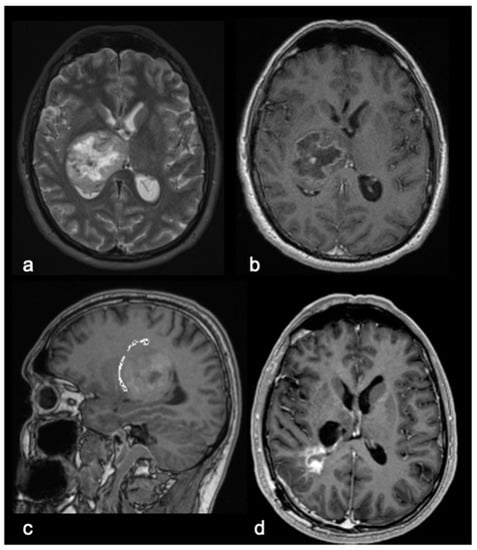

3.1. Patient Demographics, Clinical and Radiological Findings